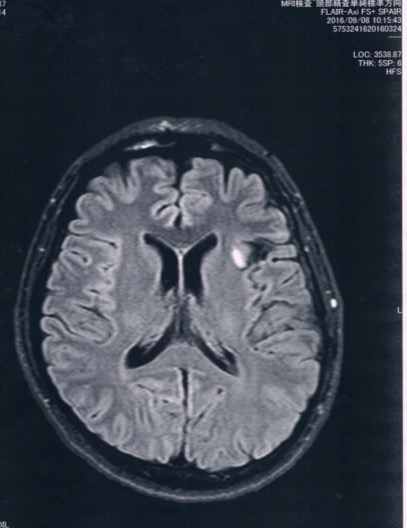

今回2016/9/8(手術後27か月)のMRI画像

今回の画像の方が、腫瘍がクッキリ写っているように見えるけど、

コントラストの違いだと思う。